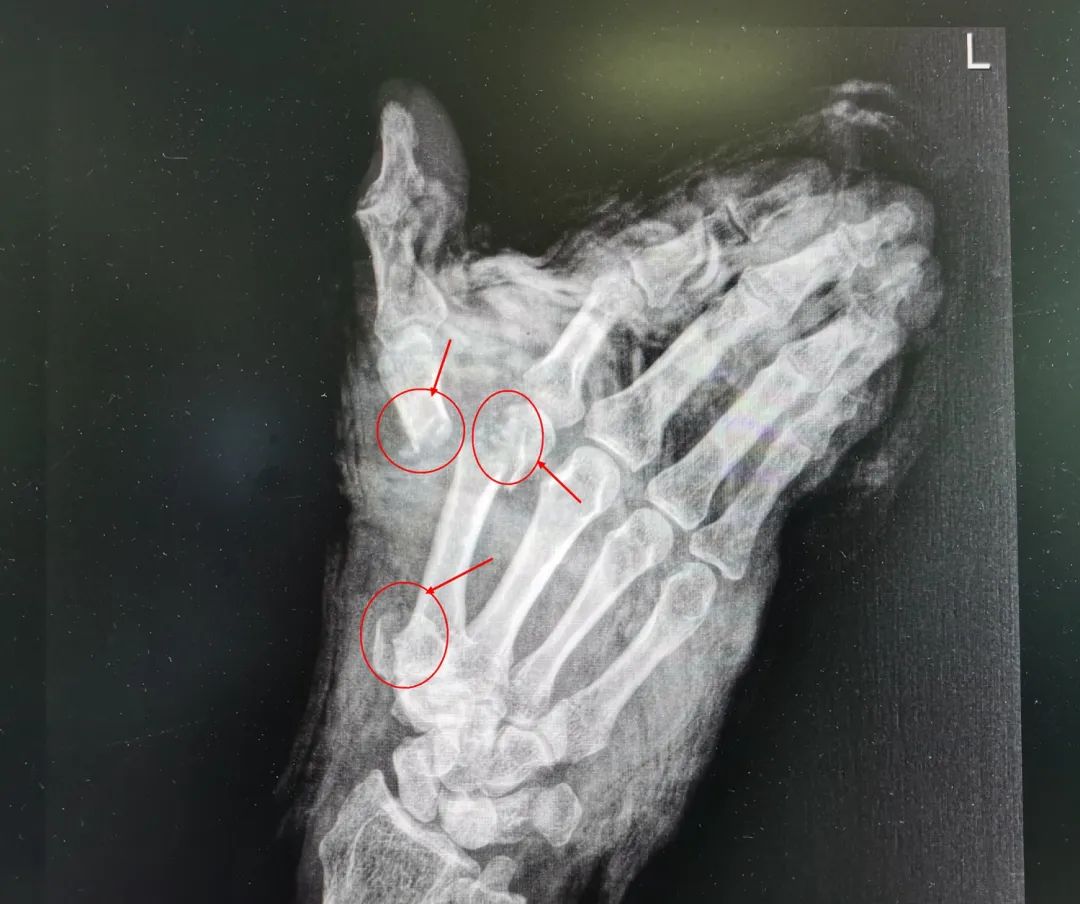

△圖為:患者術(shù)前及術(shù)后復(fù)查X光片對(duì)比

王瑞良主任介紹說,當(dāng)天晚上,楊大叔是8點(diǎn)左右來到醫(yī)院,已經(jīng)出現(xiàn)了休克癥狀。醫(yī)生觀察傷口后發(fā)現(xiàn),楊大叔的左手從大魚際處被割傷,大拇指被完全切斷,只?;⒖谔幧僭S皮膚組織與手掌相連,食指不完全離斷傷,僅近端掌指關(guān)節(jié)尺側(cè)部分軟組織相連。創(chuàng)面內(nèi)污染嚴(yán)重, 離斷血管、神經(jīng)、肌腱、骨頭外露?!皵嗾圃僦策@類手術(shù)是跟時(shí)間賽跑的手術(shù),黃金時(shí)間一般為6—8個(gè)小時(shí)。如果超過時(shí)限,手部神經(jīng)和肌肉就會(huì)壞死,所以我們立即給他進(jìn)行了手術(shù)?!?/span>

積極抗休克治療同時(shí)緊張有序的術(shù)前準(zhǔn)備之后,醫(yī)生仔細(xì)地為楊大叔進(jìn)行清創(chuàng)、骨折復(fù)位固定,耐心地吻合每一根血管、肌腱、神經(jīng),手術(shù)結(jié)束時(shí),已是凌晨。經(jīng)過三個(gè)半小時(shí)的努力,斷掌再植完成,楊大叔手指血運(yùn)逐漸良好,顏色也變得紅潤。